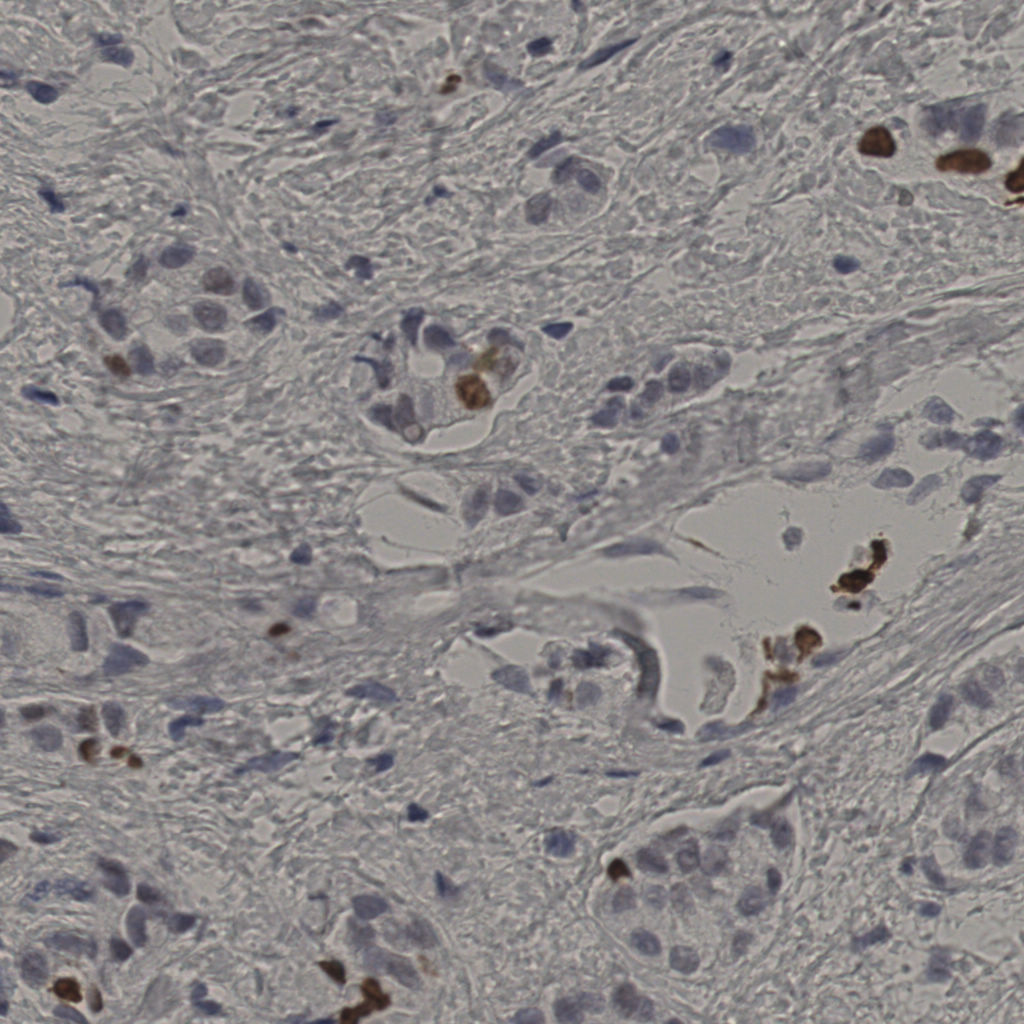

5.31%

Ki67 指数

阴 19502

阳 1093